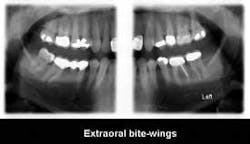

Extraoral bitewing radiographs (Fig. 4): This concept, currently available from PLANMECA USA and Sirona, shows the teeth, the periapical areas, and the related bony structures. These images are very educational for patients, and allow better diagnostic capability for practitioners than intraoral bitewings.